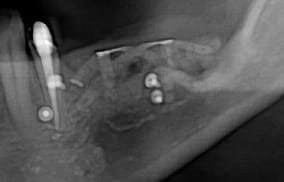

Puisqu'on parlait de ROG verticale, en voici une toute fraiche de ce matin, comblement osseux 50/50 os autogène et Bio-oss le toute recouvert par une membrane PTFE armé titane pinsé.

Plus que 9 mois à attendre ;)